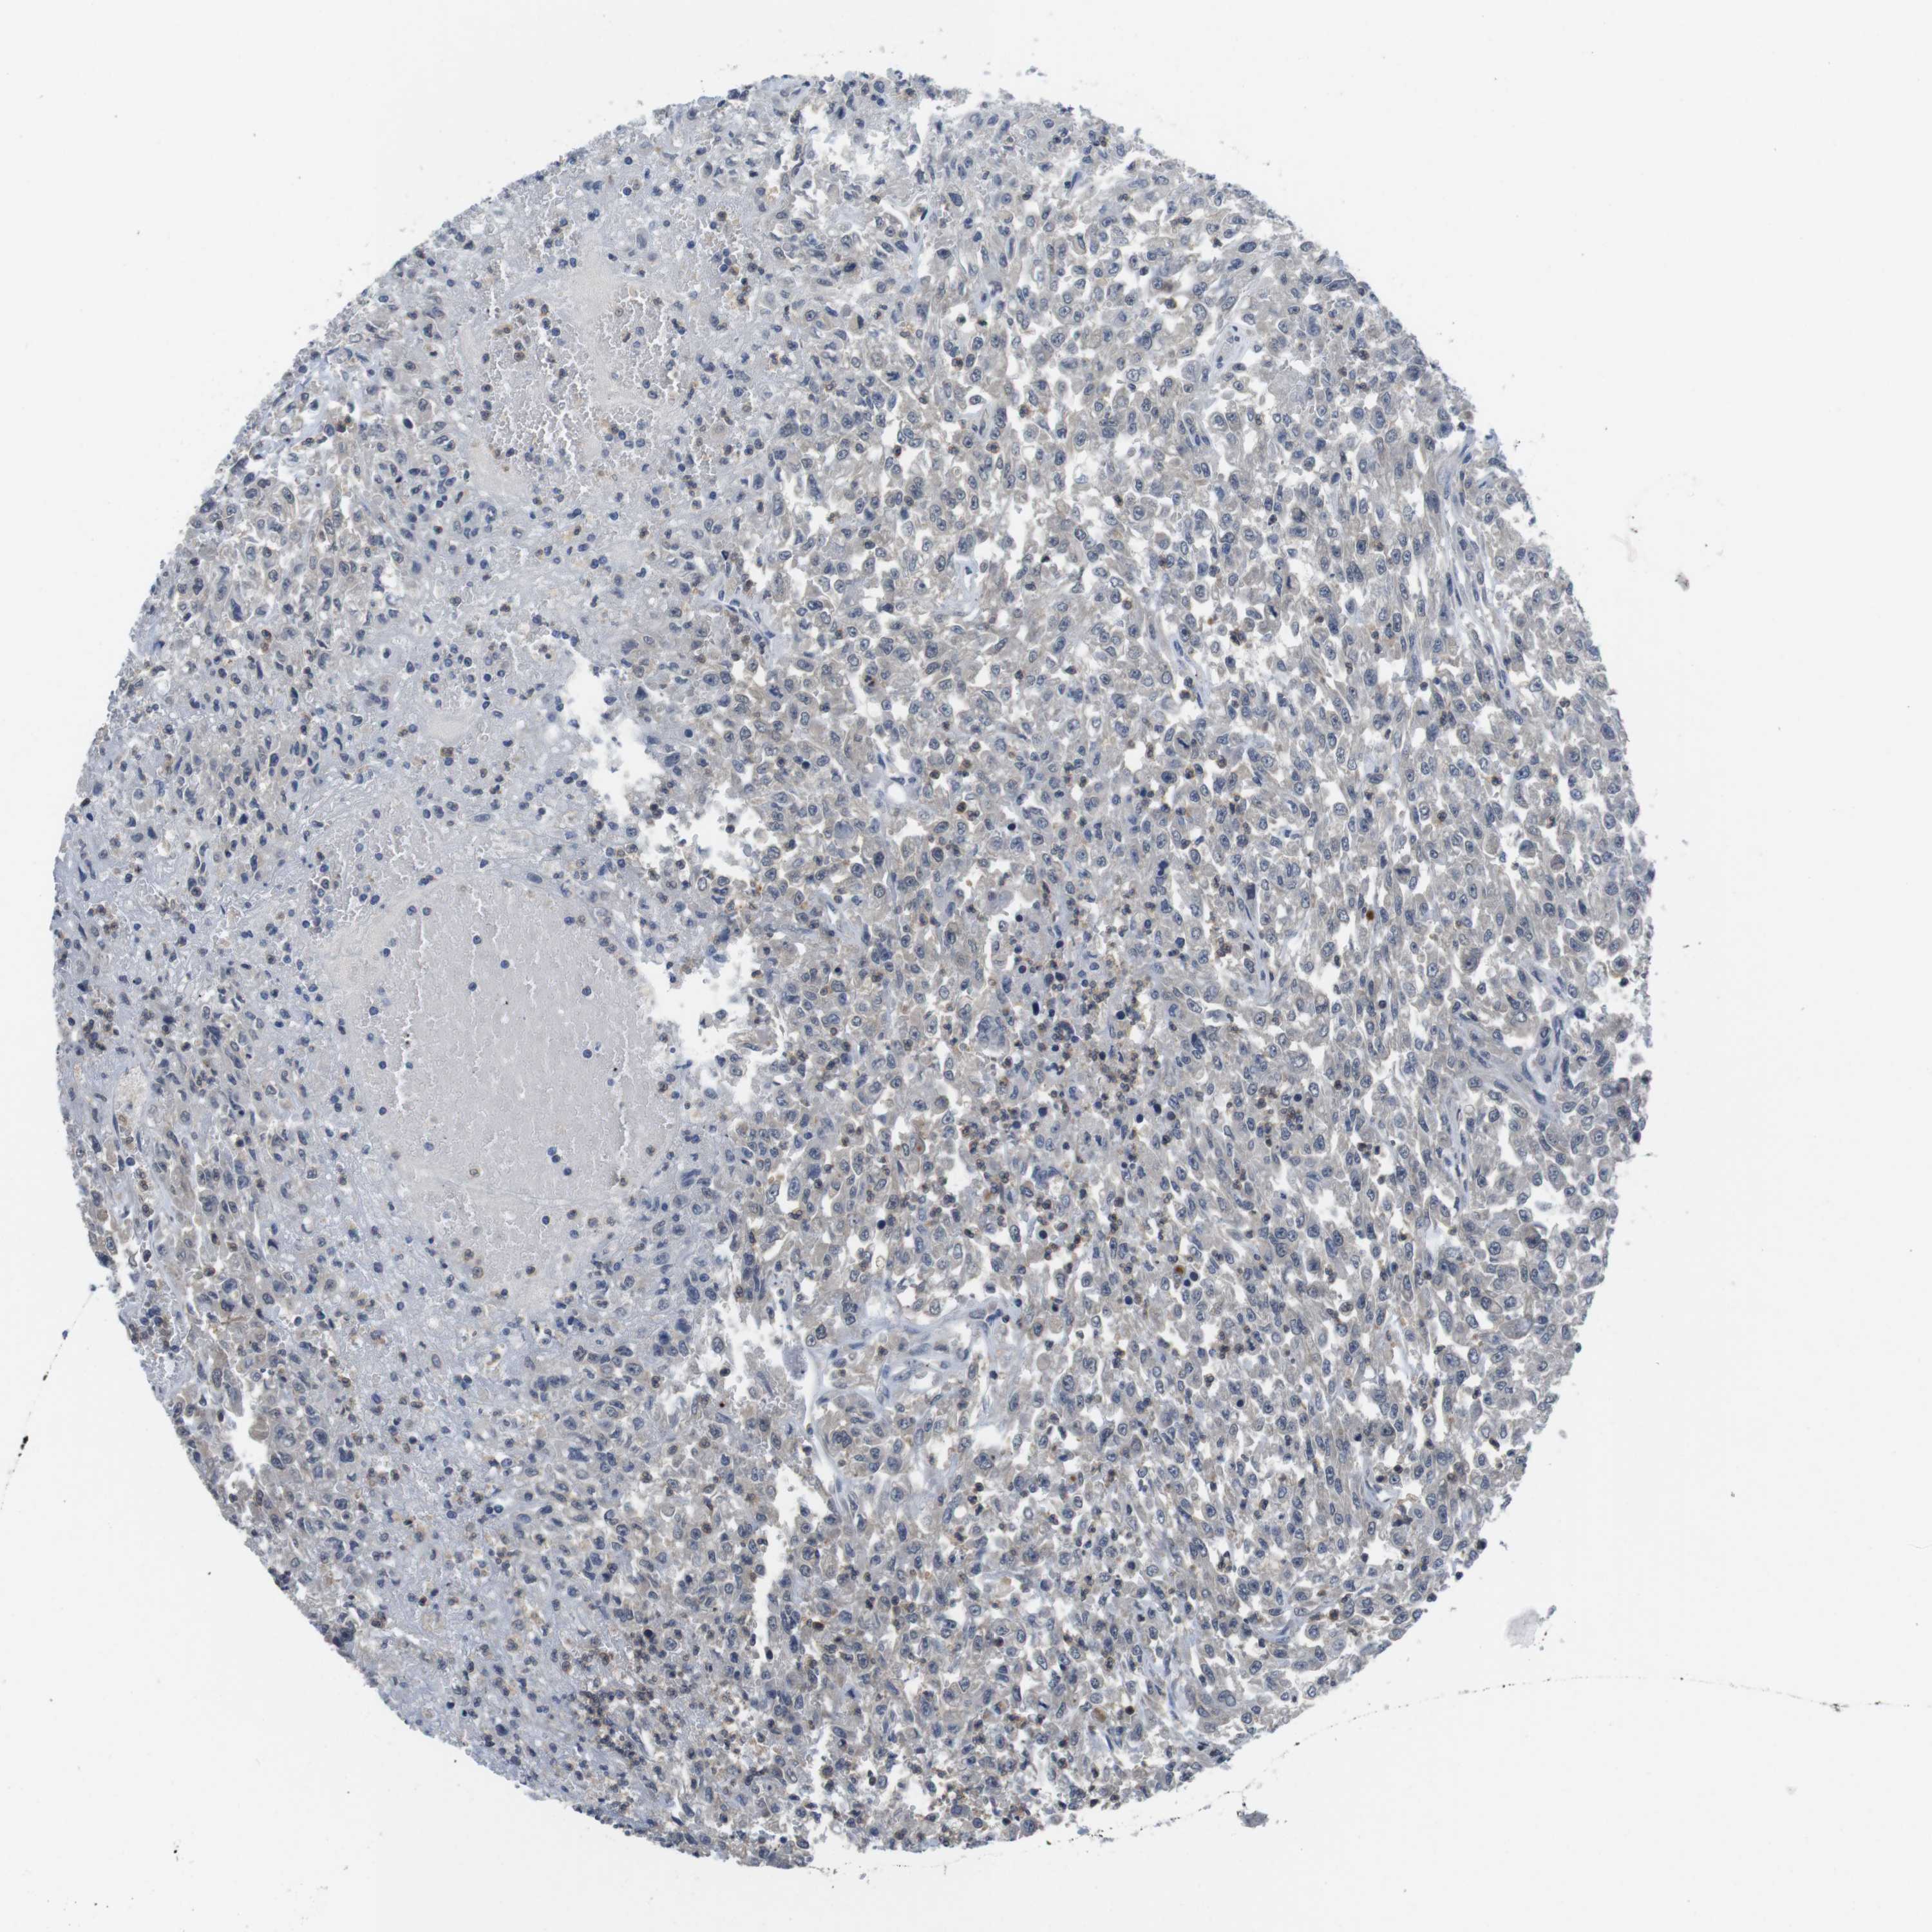

UROTHELIAL CANCER - Protein expressioni

A mouse-over function shows sample information and annotation data. Click on an image to view it in a full screen mode. Samples can be filtered based on level of antibody staining by selecting one or several of the following categories: high, medium, low and not detected. The assay and annotation is described here.

Note that samples used for immunohistochemistry by the Human Protein Atlas do not correspond to samples in the TCGA dataset.

Antibody stainingi

Antibody staining in the annotated cell types in the current human tissue is reported as not detected, low, medium, or high, based on conventional immunohistochemistry profiling in selected tissues. This score is based on the combination of the staining intensity and fraction of stained cells.

Each image is clickable and will lead to virtual microscopy that enables deeper exploration of all samples and also displays staining intensity scores, fraction scores and subcellular localization as well as patient and tissue information for each sample.

Antibody HPA001464

Antibody CAB010209

Urothelial carcinoma, Low grade

Urothelial carcinoma, High grade